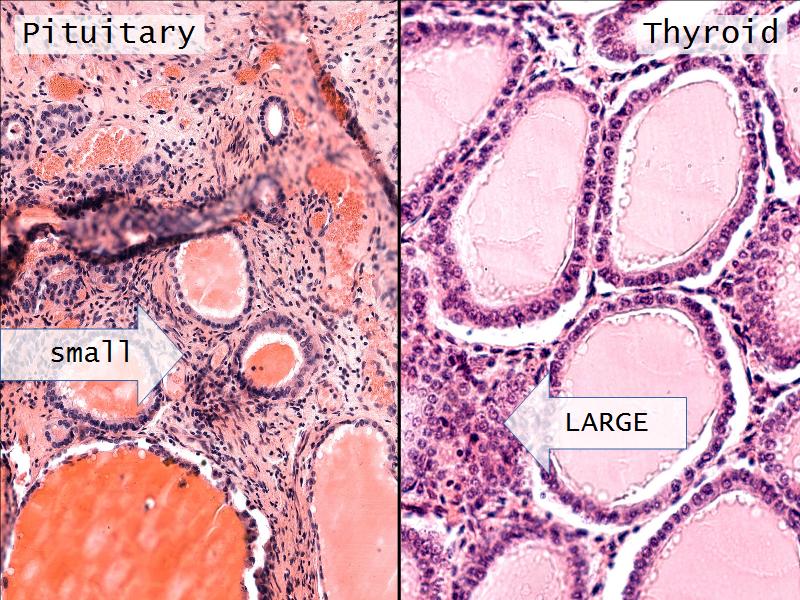

- Slide 52: Pituitary gland

- Slide 55: Thyroid gland

Pituitary gland

Thyroid gland

Four elements making up the thyroid

Thyroid gland